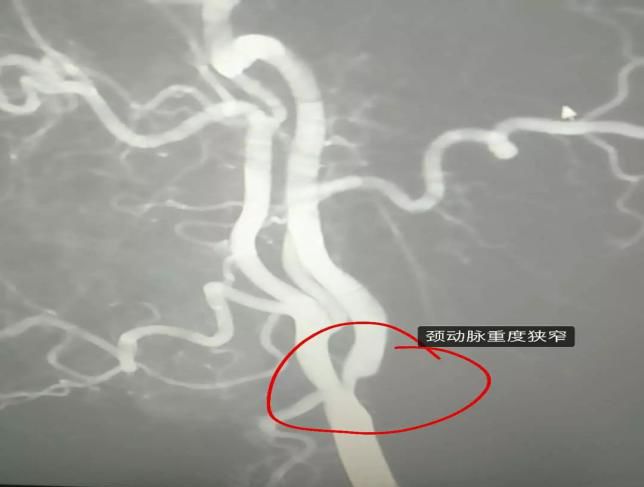

(4)2019年3月8日开展第一例颈内动脉支架植入术

患者:朱某 男性 59岁 曲梁镇

图片

术前

术后